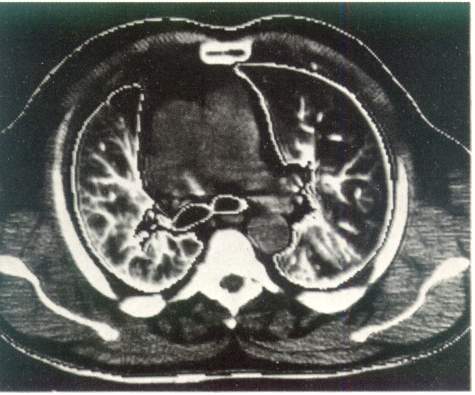

Рис. 3. Компьютерная томография органов грудной клетки. Норма.

Компьютерная томография дает возможность получить наиболее полную рентгенологическую информацию об опухолях и кистах средостения, сосудистых изменениях в легких, аневризмах, о состоянии трахеобронхиального дерева, характере и структуре «шаровидных образований в легких», патологических изменениях в плевре, грудной стенке, особенно при ее злокачественных поражениях (рис. 3).